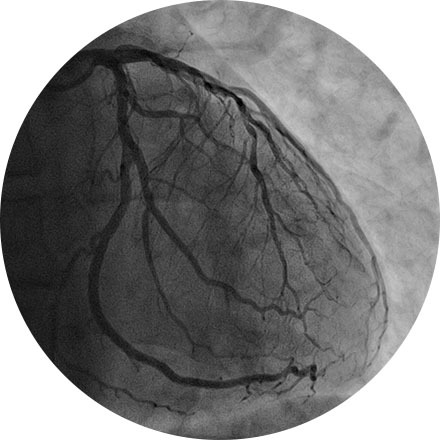

Angiogram

An angiogram is an X-ray exam of the arteries and veins to diagnose blockages and other blood vessel problems. It can reveal the integrity of the cardiovascular system in specific areas throughout the body. Combined with the use of intravenous contrast medium injected via a catheter, an angiogram identifies areas of blockage or damaged vessels within the circulatory system. CT and MRI may also be used to gain additional images of the arteries.